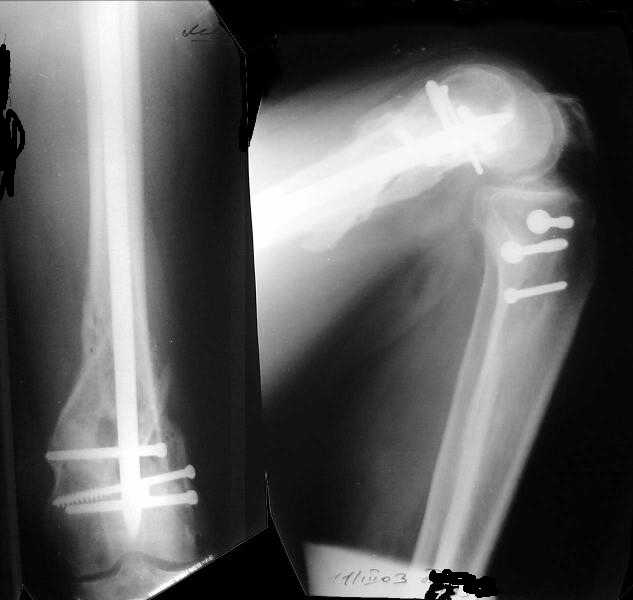

I attached an example of C2 fracture with result of the same technique in 5 months.